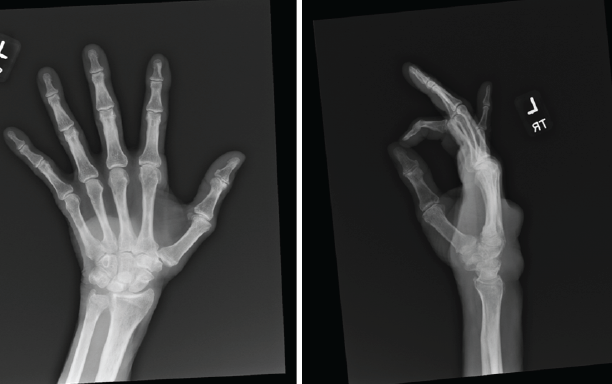

A 79-year-old male presented to our hand clinic in February 2024 for evaluation of a left dorsal hand mass (Fig. 1). Plain radiographs taken at presentation (Fig. 2 and 3) showed a small subchondral cyst and mild erosions at the distal radio-ulnar joint, along with the dorsal soft tissue swelling consistent with the clinical exam.

Figure 2 & 3: Plain radiographs taken preoperatively show a small subchondral cyst and mild erosions at the distal radio-ulnar joint.